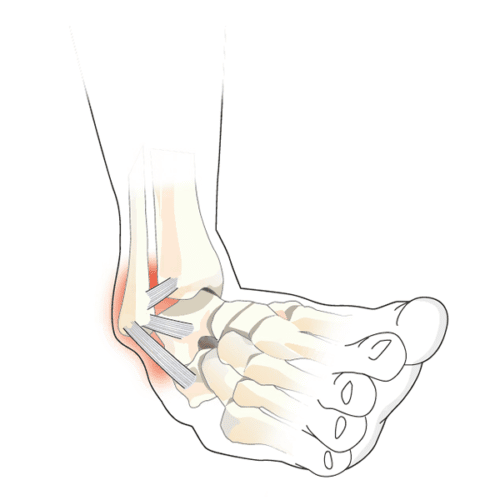

La cheville, ce pivot discret du quotidien, tient debout grâce à une architecture de ligaments. Le ligament latéral externe, placé à l’extérieur du pied, limite l’excès de torsion vers l’intérieur. Son pendant, le ligament latéral interne, stabilise la face opposée. Une entorse survient lorsque l’un de ces câbles fibreux s’étire ou se rompt sous l’effet d’un traumatisme. La gravité dépend du geste, de la force de l’accident, et du ligament touché.

La récupération d’un ligament n’est jamais identique d’une personne à l’autre. Plusieurs paramètres entrent en jeu : la nature du ligament, sa localisation précise, et l’intensité du choc initial. Par exemple, le ligament latéral interne (ou deltoïde) s’en sort souvent mieux après une entorse, grâce à ses attaches larges sur la malléole, l’astragale et le calcanéum. À l’inverse, le ligament externe est plus vulnérable : son faisceau antérieur, formé de deux bandes fines, ne cicatrise pas toujours s’il est totalement rompu.

Si ce faisceau antérieur se rompt, tout n’est pas perdu pour autant. D’autres ligaments (le calcanéo-fibulaire et le talo-fibulaire postérieur) peuvent compenser et maintenir la stabilité articulaire. Toutefois, il reste indispensable de consulter pour évaluer le risque d’instabilité persistante, et décider si des examens d’imagerie (comme une IRM) sont nécessaires, surtout si la douleur ne faiblit pas après six semaines.